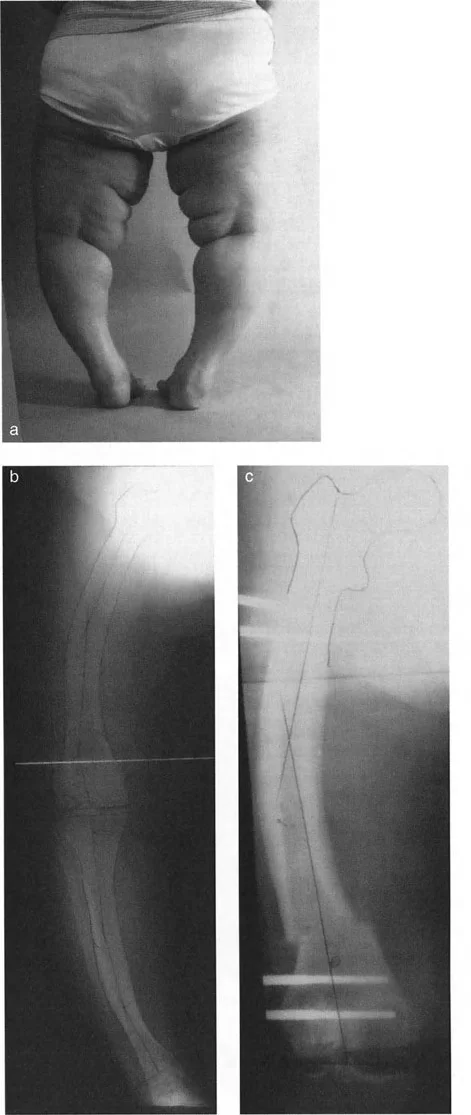

تثبيت المسمار الداخلي بمساعدة المثبت الخارجي (FAN) هو تقنية جراحية حديثة تجمع بين دقة المثبت الخارجي المؤقت واستقرار المسمار الداخلي الدائم، مما يوفر تصحيحًا فائقًا لتشوهات العظام المعقدة مع راحة فورية للمريض وتعافٍ أسرع.

الخلاصة الطبية السريعة: تثبيت المسمار الداخلي بمساعدة المثبت الخارجي (FAN) هو تقنية جراحية حديثة تجمع بين دقة المثبت الخارجي المؤقت واستقرار المسمار الداخلي الدائم، مما يوفر تصحيحًا فائقًا لتشوهات العظام المعقدة مع راحة فورية للمريض وتعافٍ أسرع.